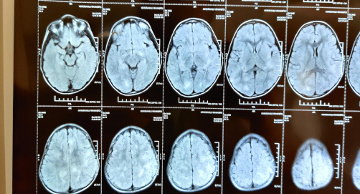

5years old boy with normal development history came with features of altered sensorium and frequent seizures. He went into status epilepticus requiring multiple antiepileptic medications and was ventilated for 7 days. His MRI brain and spine was suggestive of acute disseminated encephalomyelitis(ADEM). The antibodies for NMOSD(NMO and anti-MOG antibodies) were negative.He was treated with injection methylprednisolone and IVIG(immunoglobulin). Now after discharge he has become as normal as before.